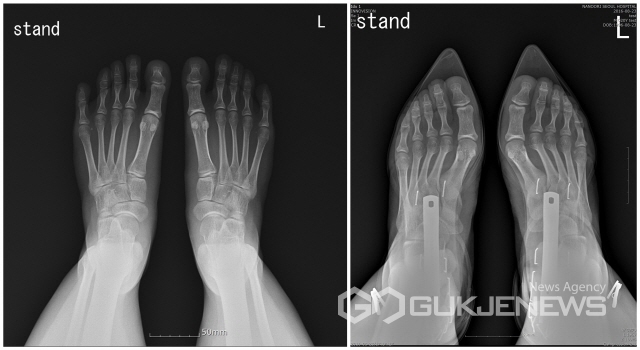

[흥미돋]하이힐 신은 발 엑스레이

• 작성자이성애강요를멈춰주세요 | 작성시간 23.05.06 현대판 전족 그 잡채

• 작성자아이텐팃티 | 작성시간 23.05.06 와 예전엔 나도 신고 다녓는데 지금보니까 전족보는 기분임 ㅋㅋㅋ